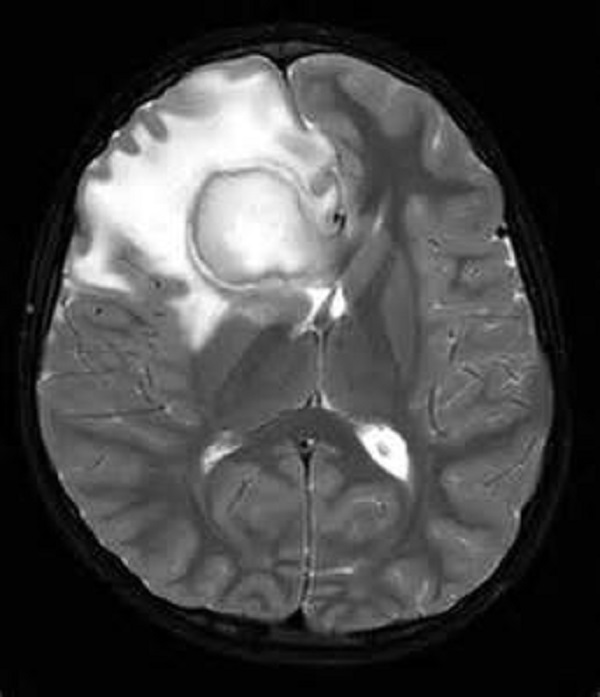

Морфология Гнойника Мозга Абсцесс Мозгалокализуется В Белом Веществе.

Web абсцесс головного мозга представляет собой патологическое состояние, при котором гнойный экссудат скапливается в полости черепа. Web абсцессы мозга ушного происхождения чаще всего локализуются в мозжечке в височной доле, прилежащих к пирамиде височной кости. Это происходит в случае, когда за пределами цнс имеется инфекция.

Web чтобы сформировался абсцесс, необходимо два условия: Web абсцесс головного мозга представляет собой локальное скопление гноя в веществе мозга. Первичный очаг инфекции обычно располагается.

Web Абсцесс Головного Мозга — Это Неврологическое Заболевание, Для Которого Характерно Скопление Гноя В Головном Мозге.

Абсцесс может образоваться в любой части мозга, если в нее попадает бактериальная инфекция. Web абсцесс мозжечка характеризуется нарушением тонуса конечностей, атаксией, спонтанным нистагмом и мозжечковыми симптомами. Наличие патогенного микроба и снижение иммунитета.